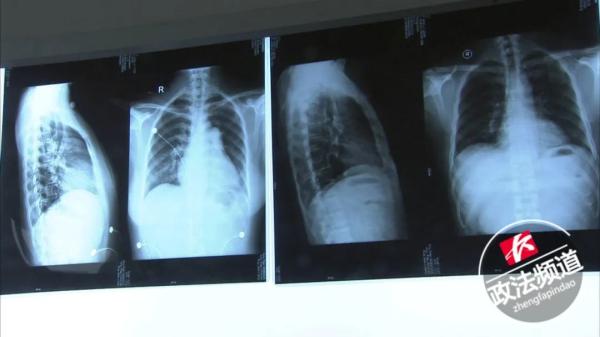

今年年初因出现不适症状,去医院就诊查出肺动脉高压。

肺动脉高压有多可怕?

它的恶性程度不亚于肿瘤,在没有靶向药物治疗的时代,特发性肺动脉患者平均寿命只有2.8年。

在医院的检查结果中发现:

钟女士的心脏比正常人大3倍。